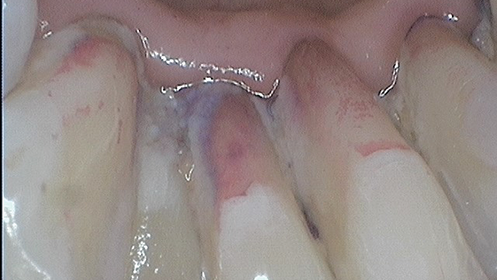

As clinicians, we should prevent scratching surfaces or creating mineral loss while removing biofilm, both of which could ultimately leave the surfaces more plaque- or stain-retentive. Flemmig et al. reminded clinicians in a 2007 study that “abrasion on tooth surfaces might become substantial over time, when the cumulative effects of repeated instrumentation during SPT [supportive periodontal therapy] are considered.”1

Clinicians traditionally mechanically debride biofilm and calculus simultaneously using repetitive, overlapping strokes followed by polishing pastes. Thirty years ago, there weren’t many other options, but just like the technological advances in dentistry—e.g., digital radiographs, scanning devices to replace alginate impressions, and technology to move teeth with computer-generated trays—GBT is a system that replaces the antiquated methods of professional biofilm management. From a comfort perspective, GBT is ergonomic for the clinician and preferred by patients compared to biofilm management with ultrasonic or hand instrumentation.3

Another benefit of biofilm management via GBT is efficiency when implementing the eight-step system. Since clinicians remove biofilm from surfaces early on in the appointment, the need for overlapping, repetitive strokes using power or hand instrumentation is substantially reduced. Total debridement time is less, which allows extra time for additional services and patient education. The patient experiences less mechanical instrumentation with GBT, yet enjoys the optimal outcome of smooth, clean surfaces.